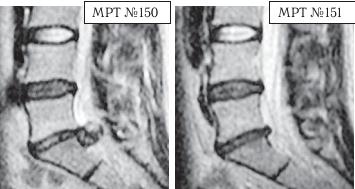

Вот ещё один любопытный результат из этого раздела документальной медицинской информации, который заслуживает внимания.

На МРТ № 150 в поясничном отделе позвоночника наблюдается рецидив грыжи после перенесённых пациентом двух хирургических операций: секвестрированная грыжа межпозвонкового диска в сегменте LV-SI .

На МРТ № 151 наблюдается состояние поясничного отдела позвоночника после одного курса лечения методом вертеброревитологии.